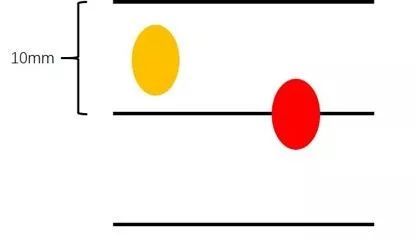

常规CT平扫是目前临床应用最广泛的CT平扫,对设备要求低,绝大多数基层医院也有配备,价格也最便宜,一般体检所做的胸部CT即是这种。普通CT平扫的层距通常为8-10mm,故扫描速度也比较快,多应用于急诊。设备的新旧决定了图像的清晰程度,较先进的设备可以发现肺部小结节,不过由于其过宽的层距,很有可能会将肺小结节漏诊,特别是小于10mm 的结节(目前小于10mm的早期肺癌发现率不断提升)。

(当层距为10mm时,对于小于10mm的结节,图中黄色结节就会被漏诊,红色结节被检出。)